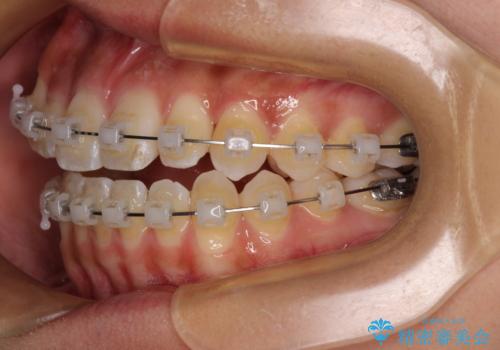

八重歯とオープンバイト 急速拡大装置を用いた矯正治療

- 前歯の開咬と、上顎前歯の八重歯やデコボコを気にして来院された患者様です。

上顎歯列が狭窄していたため、急速拡大装置により上顎骨を側方に拡大し、その後ワイヤー装置にて矯正治療を行うこととしました。

急速拡大装置で上顎骨を十分に拡大できたことで、非抜歯で八重歯を歯列に納めることができました。